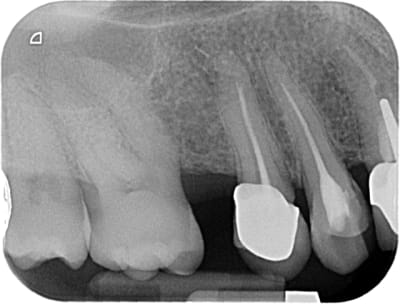

11 et 21 sont vitales.

pour le haut je ne suis pas sur que la forme de la 12 soit très esthétique,

ainsi est-ce que refaire la 12 et cc pour 22 21 11 parait pertinent ?

sauf que si on refait 12 en gardant l'inlay-core ( je suis toujours prudent avec les déposes !!), cela vaut-il le coup de faire des cc ?

22 21 et 11 ce sont des indications de facettes, pourquoi mutiler complètement la dent ?

4 facettes.

les couronnes dans la foulée ou +tard suivant ses moyens et envies.

Pour la 22 qui est intacte, pourquoi pas. Pour les deux autres, à partir du moment où on a un composite proximal qui va également sur la face palatine, j'estime que la couronne est mieux indiquée. Le jour où on aura une infiltration, on sera bien embêté. Pourquoi s'empêcher de soigner totalement quelqu'un sous des prétextes intellectuels.